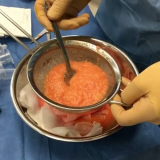

Lipoaspiração a Laser

Você merece a qualidade e comprometimento entregues pela equipe deste consultório médico e se neste momento está à procura de uma equipe que realize lipoaspiração a laser saiba que a FF Cirurgia Plástica disponibiliza de imediato este serviço para você!

Lipoaspiração a laser: atendimento eficiente e com qualidade que você sempre buscou!

Neste consultório médico você encontrará profissionais eficientes e com experiência de excelência. Usufrua de bom atendimento, através dos melhores preços do mercado e de assistência especializada sempre à sua disposição! Leve as suas dúvidas, converse com a equipe da FF Cirurgia Plástica. Contrate bons serviços e sinta-se mais seguro para cuidar da saúde.